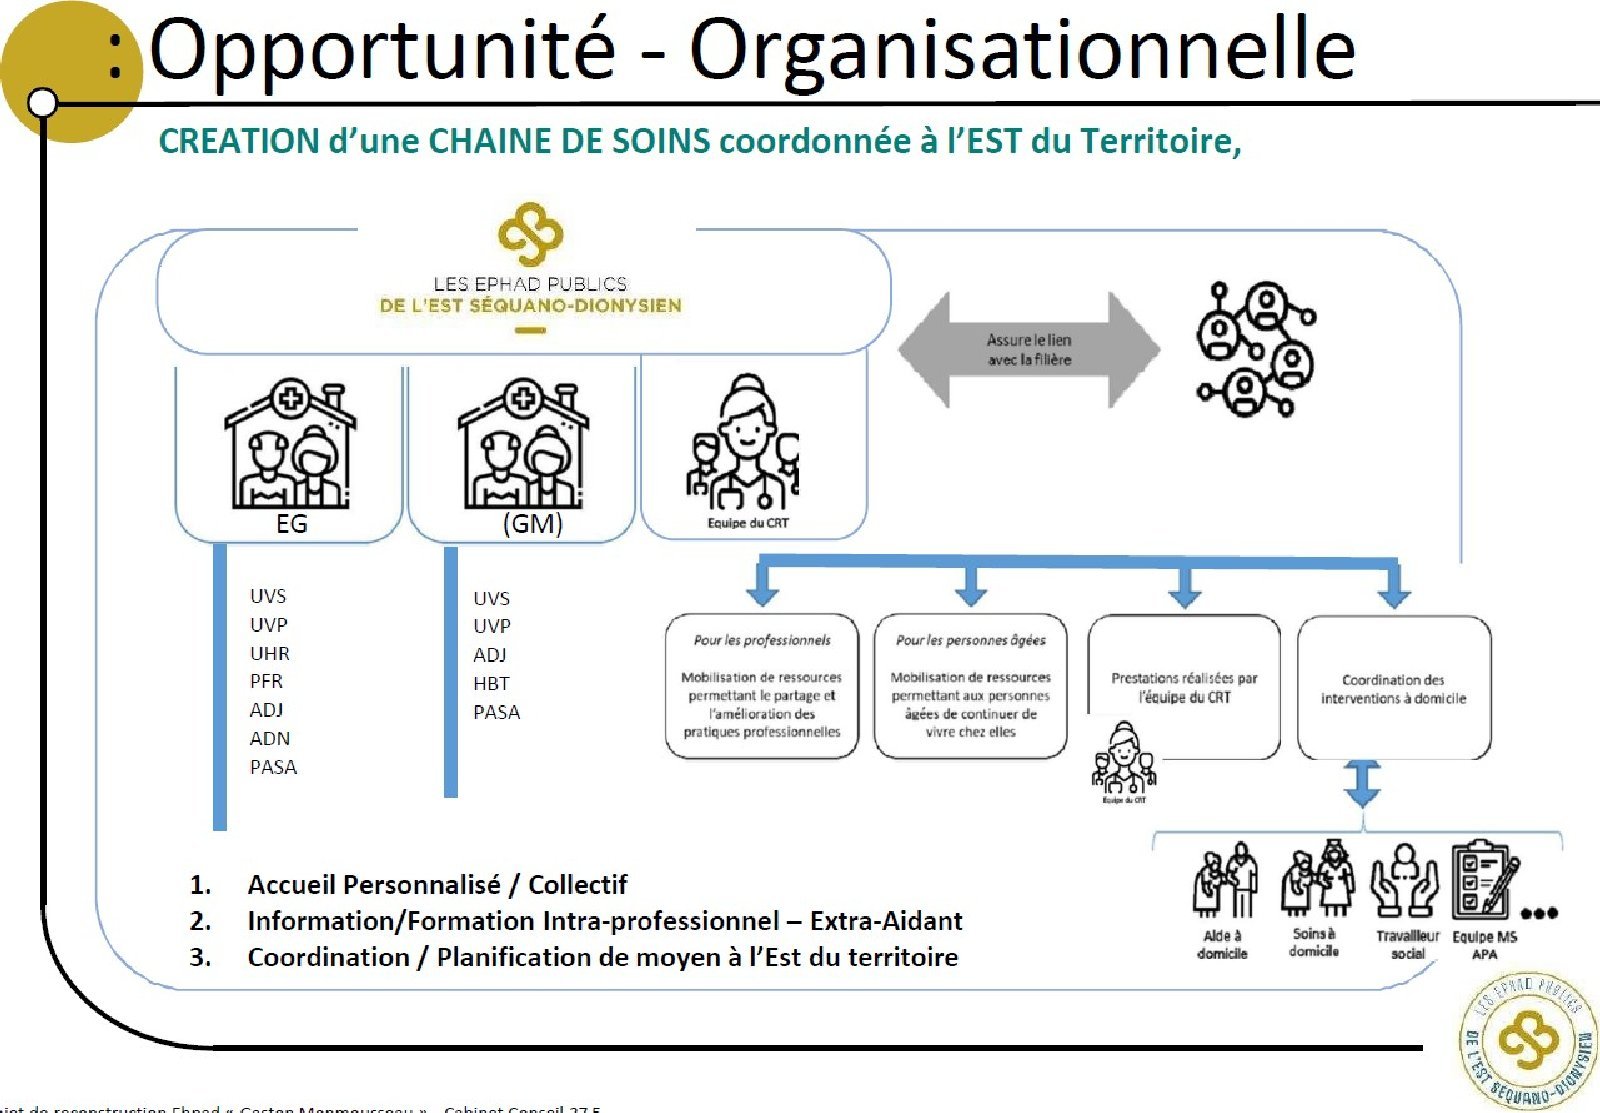

Ehpad EG

EN COURS AMo - Emile Gerard

Ehpad GM